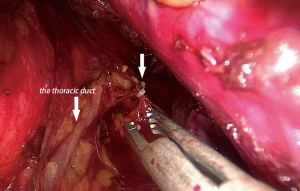

A total of 60 patients underwent esophagectomy via transcervical incision inflatable single-port mediastinoscope combined with laparoscopy, and the tumors were completely resected. No perioperative death and no aortic injury occurred among the patients. Bronchial artery injury and hemorrhage occurred in 2 cases (3.33%). Bleeding was stopped in a case after compressing for 15 minutes with a gauze strip by introducing a mediastinoscope. In other case, stopping the hemorrhage was not successful with compression; and therefore, the method was converted to video-assisted thoracoscopy, and the bleeding was stopped successfully by suturing the bleeding artery. The bronchial artery combined with azygos vein hemorrhage was observed in a case (1.67%). Hemostasis with energy devices and packing remained unsuccessful (Figure 4). Hemorrhage was severe and unable to control through the mediastinoscope. Emergency conversion to thoracotomy was done, and the source of bleeding from the azygos vein that was controlled by clamping and repairing by vascular suturing. Right pleural injury was observed in 3 cases (5%), and so pleura were opened during dissection of the right esophageal wall, and no special treatment was needed (Figure 5). Recurrent laryngeal nerve injury was observed in 7 cases (11.67%). Hoarseness of voice was noticed post-operatively, and was recovered without any special treatment from 6 months to 1 year after the operation. Thoracic duct injury was observed in 1 case (1.67%), which led to leakage of lymph in the operative field under mediastinoscopy. The thoracic duct was dissected at T10 and clipped by Hemolock applicator (Figure 6). The patient had no chylothorax after operation. There was no tracheal or bronchial injury in this series.

Thoracic duct injury is a common complication during esophageal surgeries, in which it can lead to postoperative chylothorax. The incidence of thoracic duct injuries during open surgery for esophageal cancer is about 1.06% to 1.35% (15,16). The incidence of thoracic duct injury in this study is 1.67%. Due to the influence of sample size and other reasons, whether the difference between the data is meaningful or not requires further study. The most common place of injury is at T5 level, wherein the duct crosses the midline in front of the vertebral body. The improper use of energy devices and tumor invasion can easily damage the thoracic duct. The branches of thoracic ducts are occasionally injured due to high variation in the anatomy of thoracic duct. Wan Pernis has suggested that the thoracic duct is always present solely at level 8 of the thoracic vertebra to the cisterna chyli, and so when the thoracic duct is suspected to be injured during the operation, then the thoracic duct can be ligated at level 10 of the thoracic vertebra in order to prevent the occurrence of chylothorax (15). A preoperative high-fat diet can effectively fill the thoracic duct to show its course clearly during the procedure, reducing the chance of its damage (13).